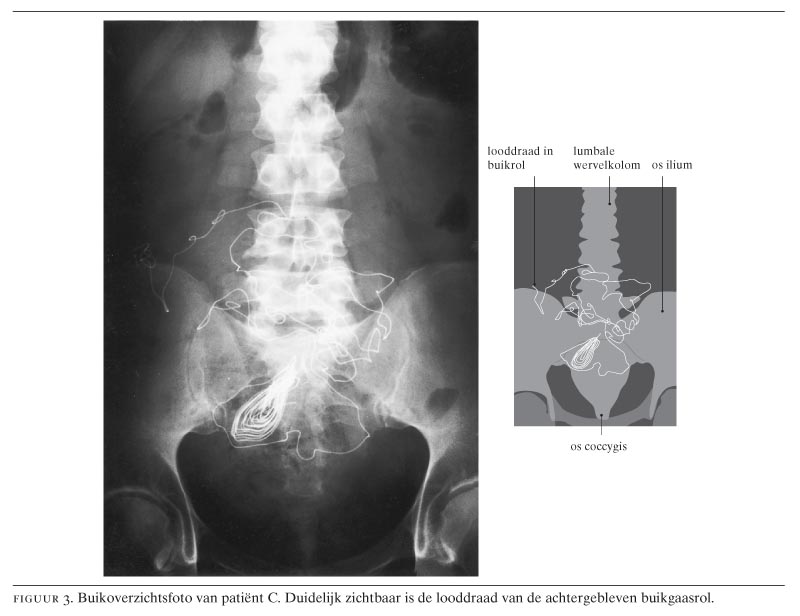

Patiënt A, een 36-jarige man, werd gezien op de Spoedeisende Hulp in verband met een sinds drie weken bestaande zeurende pijn in de onderbuik. Bij lichamelijk onderzoek bleek hij ziek, en er was een forse zwelling in de onderbuik, waarvan de bovengrens tot aan de navel reikte. Er bestond een percutoire demping over de gehele onderbuik. Rectaal toucher was zeer pijnlijk in de richting van de excavatio rectovesicalis (cavum Douglasi). De voorgeschiedenis vermeldde een partiële darmresectie 15 jaar eerder in Spanje, waarschijnlijk vanwege een ileus. De buikoverzichtsfoto liet geen afwijkingen zien. Echografie van de onderbuik toonde een cysteuze tumor met afmetingen van 11 × 14 × 22 cm, met interne reflecties. Op de CT-scan werd een cysteuze tumor gezien, waarbij de blaas werd verdrongen naar links anterolateraal, met een lichte dilatatie van beide ureteren en beide nieren (figuur 1). In de buik werden geen andere afwijkingen aangetroffen.

Voor de diagnostiek van achtergebleven gazen komen röntgenfotografie, echografie en CT in aanmerking. Op röntgenfoto's zijn alleen gazen met looddraad en met ontstekingsprocessen (ten gevolge van een gaas), waarin verkalking of gasvorming is opgetreden, aantoonbaar. Echografie kan een cysteuze tumor laten zien, met sterk irregulaire interne reflecties. Echter, allerlei wisselende beelden worden beschreven.6-10 De CT-scan toont meestal een scherpbegrensde massa met interne, heterogene densiteiten en een dikke perifere rand.10 In de Engelse literatuur wordt gesproken van een ‘textiloma’, ‘gauzoma’, ‘gossypiboma’, ‘cotton balloma’ of ‘gauze granuloma’.